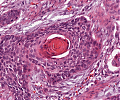

A52 Hodgkin-Lymphom

Mehrkernige Reed-Sternberg Zelle mit mit prominenten Nukleoli beim klassischen Hodgkin-Lymphom.